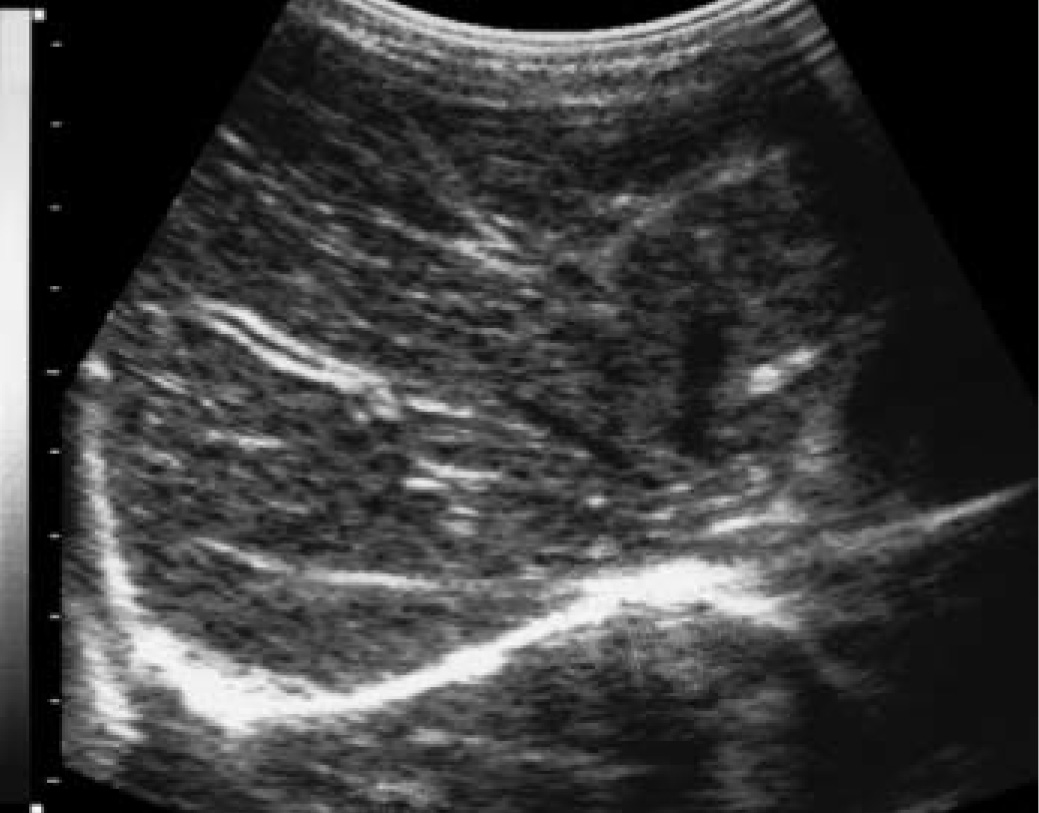

Как выглядит доля Риделя на УЗИ печени